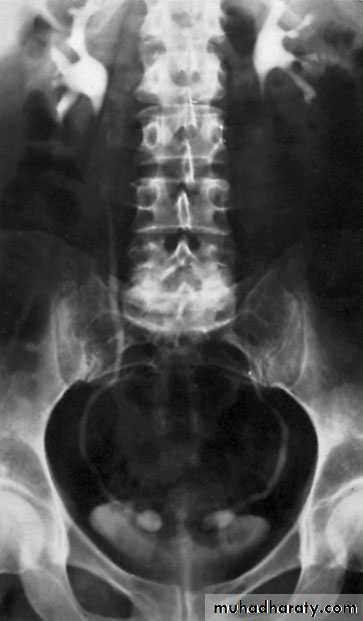

Diagnosis : U/S or IVU,CT scan: absent kidney on that side + compensatory hypertrophy of the contralateral kidney

Horseshoe Kidney

found in 1:1000 necropsies an is commoner in men.

probably the most common of all renal fusion anomalies

The anomaly consists of two distinct renal masses lying

vertically on either side of the midline and connected at

their respective lower poles by a parenchymatous or fibrous

isthmus that crosses the midplane of the body.

Fusion of the renal masses early in embryonic life, so its ascent

will be impeded by inferior mesenteric artery.

The kidneys are low located, mal rotated and pelves lie anteriorly

Diagnosis ultrasound, IVU, CT scan